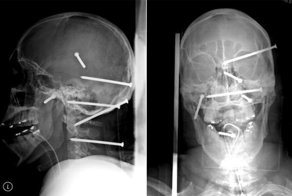

1.

Двое мужчин-строителей упали со строительных лесов. В руках одного из них был пистолет, стреляющий гвоздями, при падении пистолет сработал и выпустил кучку гвоздей в голову второго упавшего. 39-летний Исидро Мехиа ходил с минимальной помощью и говорил немного медленно, потому что речевой центр его мозга был затронут, но его прогресс прекрасен и с реабилитационной терапией он восстановился полностью.